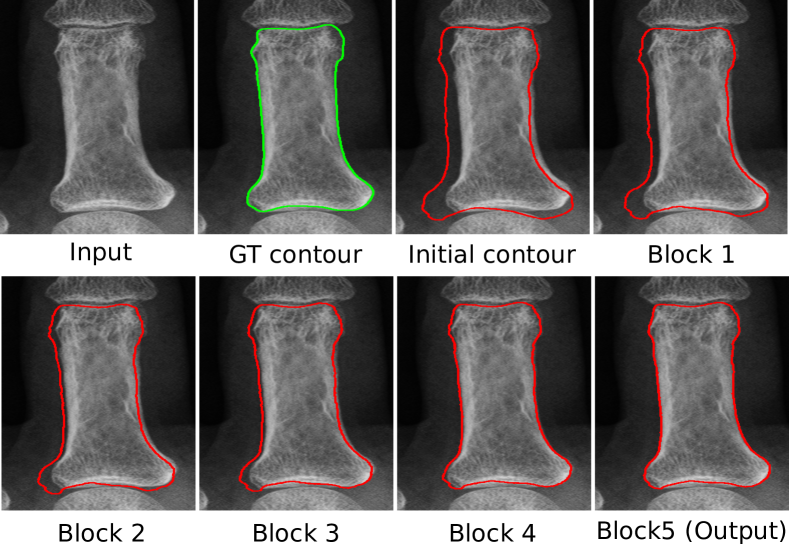

Refer to caption

Fig. 6: Visualization of the contour evolution process. The red lines are the contours after each GCN block in CTN. It shows how CTN gradually moves the initial contour to the correct location.

The results in Table 1 show that our method significantly outperforms both MorphACWE and MorphGAC. Specifically, on average we achieve 15.63% higher IoU and 20.94 pixels less HD than MorphGAC, the better of the two. The visualizations of segmentation results in Fig. 5 confirm that these two approaches cannot provide satisfactory segmentation accuracy, especially when the boundary of such structures is not clear, e.g., lung segmentation. We posit that the inferior performance of ACM-based methods is owing to two factors: 1) the gradient-based energy function is not suitable for objects without clear boundary, 2) optimizing the energy function on single image often encounters local minima (i.e., causing segmentation leakage). In contrast, CTN optimizes shape and appearance-based loss functions on an aggregated of the unlabeled dataset to achieve high robustness. Fig. 6 shows the evolution process of the CTN contour on a phalanx image.

3.7.3 Impact of the number of GCN block iterations

In this section, we evaluate the impact of the number of GCN block iterations by training and testing the CTN with 1, 3, 5, 7 and 9 GCN block iterations on the hip dataset. The results of this analysis are summarized in Table 6. It shows that as the number of GCN blocks increases from 1 to 5, the performance improves from IoU 97.10% to 97.29% and HD 8.51 px to 8.27 px, respectively. It demonstrates that by stacking multiple GCN blocks, the later GCN block can further correct the segmentation errors produced by the earlier GCN blocks, which is beneficial to the final performance. However, the performance starts to slightly degrade when the number of GCN blocks increases over 5. We posit that the increased number of layers in the CTN caused by the additional GCN blocks make the network more difficult to train, which contributes to the performance degradation.